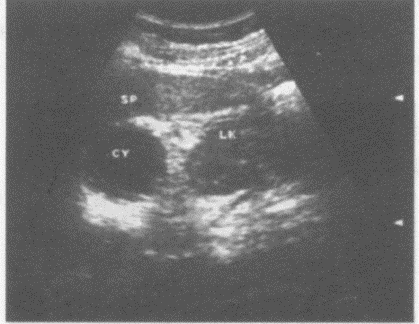

临床资料:女,55岁,常规体检。超声综合描述:左肾上极与脾之间可见3.4cm×4.0cm圆形无回声区,包膜完整,后方声加强,CDFI:内未见动静脉血流信号。

超声提示()

A:左肾囊肿

B:左肾上腺囊肿

C:脾囊肿

D:副脾